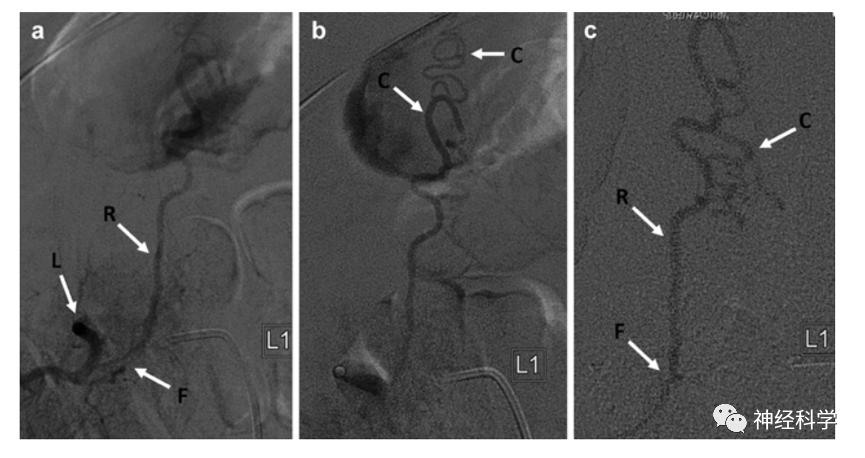

图4. 腰动脉(L)瘘点(F) 根静脉(R) 冠状静脉(C)